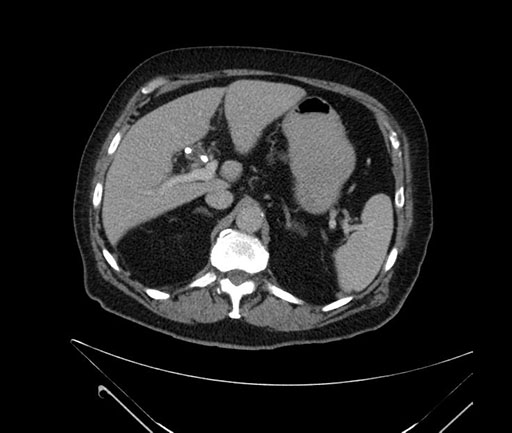

Axial - 3 months prior